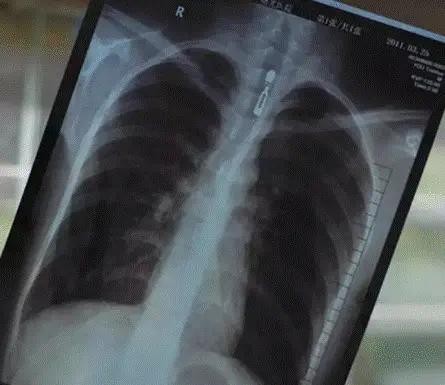

胸透的作用是非常大,能够通过观察照射的图像,观察心、肝、肺的一个情况,看看是否出现了异常,这是比较常规的检查,而女生之所以对这个排斥,是因为比较的害羞,害怕自己的隐私就这样暴露,实际上这个困扰是没有必要的。

胸透的最终成像,并不是彩色的,而是黑白的,展现在医生面前的图像,是器官的造影而已,所以女生们根本不用担心,另外大家对于一些不了解的医疗检查,可以自己去了解一下,不要着急着拒绝,因为医生的建议还是非常有用的,对此你们还有什么困扰吗?